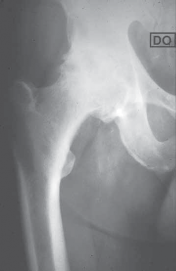

A library of advanced orthopedic surgical techniques, providing step-by-step guidance for complex musculoskeletal procedures.